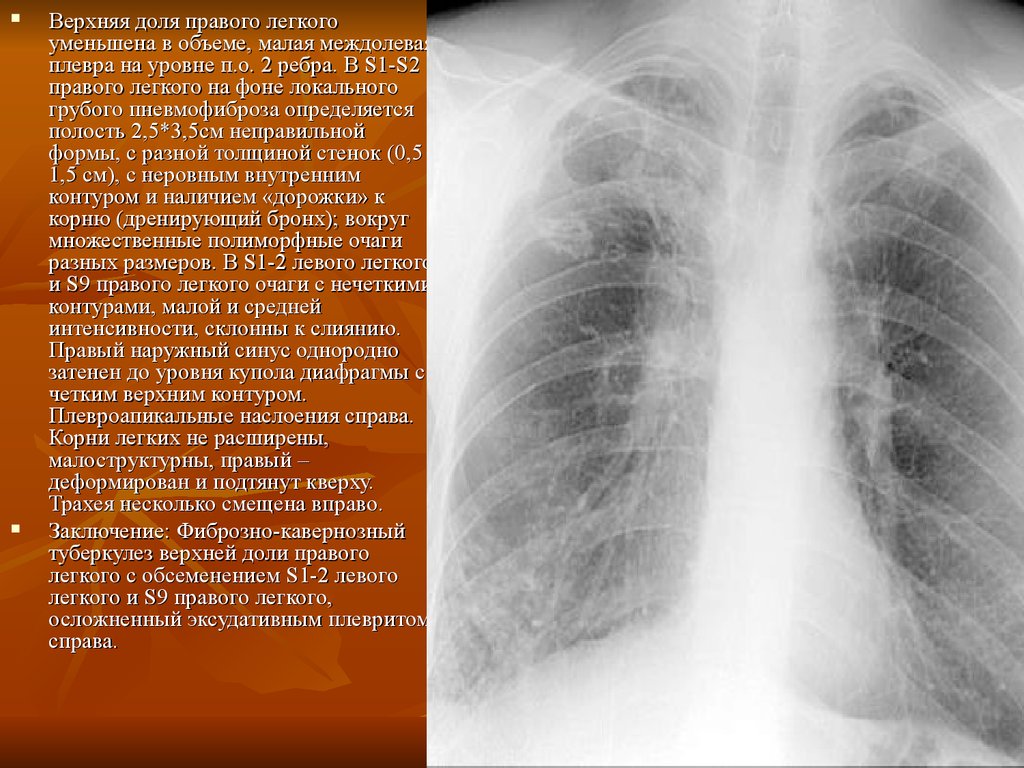

Фотографии, демонстрирующие обнаруженное усиление легочного рисунка

Раздел: Фотодневник открытий